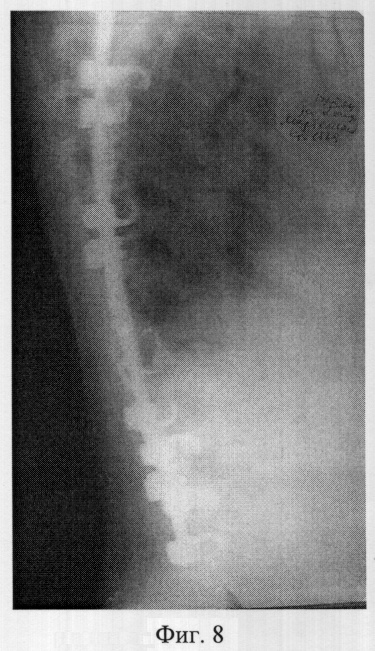

Фиг.7 – рентгенограмма в прямой проекции позвоночника больной M. после операции полисегментарной дорсальной коррекции и фиксации из заднего доступа;

Пример 2. Больная M., 15 лет, 12.10.04 поступила в клинику детской ортопедии СарНИИТО по поводу диспластического грудопоясничного правостороннего нестабильного прогрессирующего сколиоза III степени.

В СарНИИТО ей была выполнена рентгенография в стандартных проекциях: фасная (фиг.5) и боковая (фиг.6) рентгенограммы.

По фасной рентгенограмме определены показатели позвоночника:

– угол сколиотической деформации по Кобб: стоя – 63°, лежа – 48°;

– индекс стабильности по Казьмину – 0.87;

– определена протяженность дуги в 12 позвонков (от Th5 до L4),

– определена вершина деформации – Th11.

По рентгенограммам проведена оценка зрелости позвоночника: тест Риссера составил R-4, кольцевые апофизы тел позвонков не определяются на фоне тел по всей дуге искривления, что свидетельствует о завершенности роста больной.

В связи с протяженностью сколиотической дуги в 12 позвонков, локализацией центральной дуги в грудопоясничных отделах, завершенности роста больной сделан вывод о возможности проведения дорсальной коррекции сколиотической деформации и фиксации позвоночника из заднего доступа с созданием заднего спондилордеза.

Определили патологическую ротацию позвонков сколиотической дуги. Показатель патологической ротации на вершине деформации Th11 не превысил 43°, поэтому установка транспедикуллярных винтов не оправдана.

Заключение: необходимо проведение оперативной дорсальной коррекции и фиксации позвоночника двустержневой полисегментарной типа CDI «Horizon» фирмы «Medronic» с использованием дополнительных субламинарных проволочных петель

14.10.04 была выполнено запланированное оперативное вмешательство.

В послеоперационном периоде выполнены контрольные рентгенограммы: фасная фиг.6, боковая фиг.7. По фасной рентгенограмме определен угол остаточной деформации по Кобб – 23°, степень коррекции 40°, что составляет 64% от первоначальной деформации.